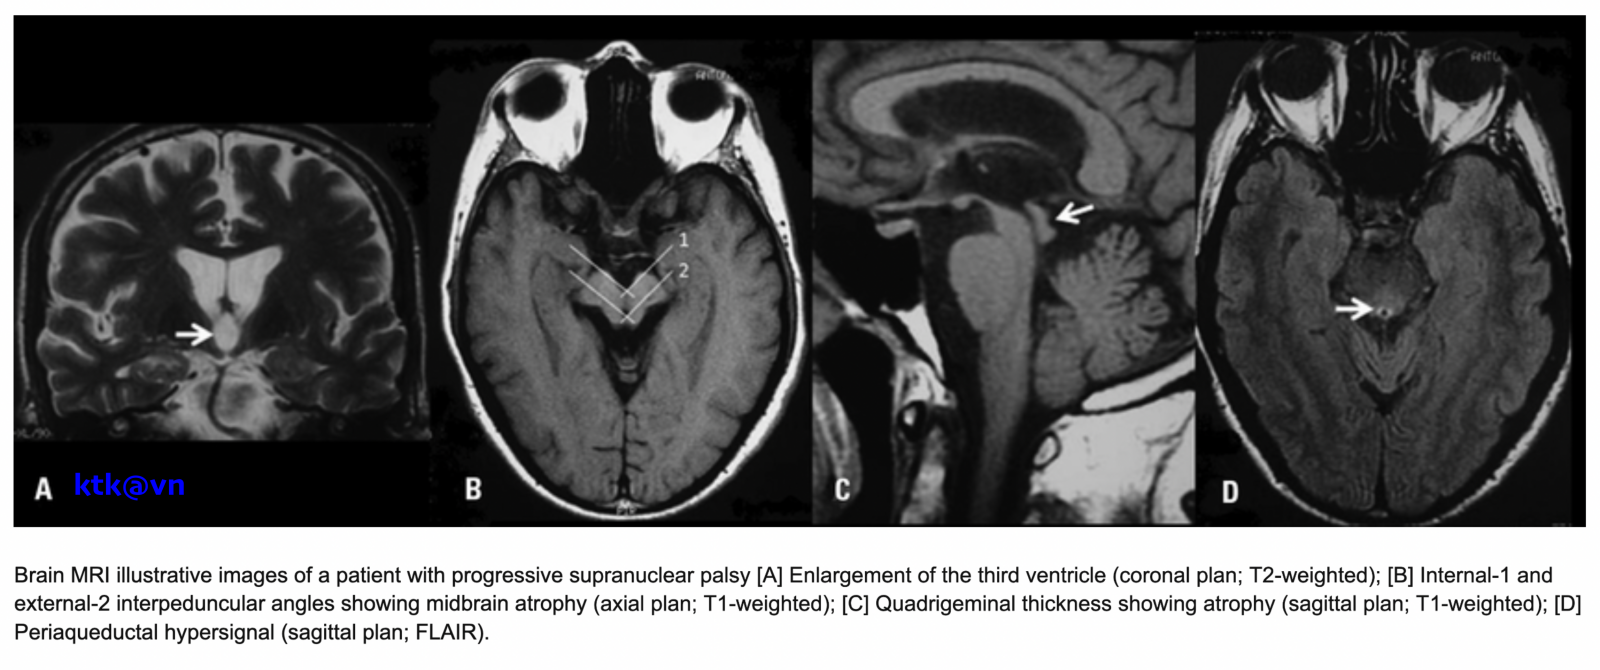

Những đặc điểm thường gặp trên hình ảnh phim chụp cộng hưởng từ sọ não là teo não giữa, giãn não thất ba, teo cuống tiểu não trên (SCP), teo thùy trán và thái dương. Teo não giữa được thể hiện trực quan qua hình ảnh “mỏ chim ruồi” khi nhìn trên lát cắt đứng dọc, hình ảnh “chuột Mickey” khi nhìn trên lát cắt ngang, hình ảnh “morning glory” (một số tài liệu gọi là dấu hiệu hoa mòng biển) trên lát cắt ngang. Teo cuống tiểu não trên, dấu hiệu “chim ruồi”, dấu hiệu “hoa mòng biển” trên cộng hưởng từ cấu trúc có độ đặc hiệu cao nhưng độ nhạy kém hơn tiêu chuẩn lâm sàng.

Các phép đo định lượng não giữa, cuống tiểu não và các cấu trúc thân não khác, đã cho thấy độ nhạy và độ đặc hiệu cao hơn:

– Đo lường chiều rộng trước sau và thể tích của cuống não của bệnh nhân PRP-RS nhỏ hơn bệnh nhân teo đa hệ thống và bệnh Parkinson. Liệt trên nhân tiến triển có giảm diện tích não giữa trên mặt phẳng đứng dọc giữa, giảm tỷ lệ cuống não/cầu não. Tuy nhiên độ nhạy và độ đặc hiệu của tỷ lệ cuống não/cầu não phân biệt PSP-RS và teo đa hệ thống thể Parkinson (MSA-P) còn dao động khác nhau giữa các nghiên cứu.

– Chỉ số parkinson cộng hưởng từ (MRPI) [= diện tích cầu não /não giữa) * (chiều rộng cuống tiểu não giữa/cuống tiểu não trên)] có độ nhạy và độ đặc hiệu cao trong chẩn đoán phân biệt liệt trên nhân tiến triển với MSA-P và bệnh Parkinson, tuy nhiên để tính được chỉ số này yêu cầu một phương pháp đo chi tiết, khó phổ biến cho các trung tâm và đưa vào thường quy.

Một số hình ảnh nhận biết Liệt trên nhân tiến triển (Phim chụp cộng hưởng từ (MRI) sọ não)